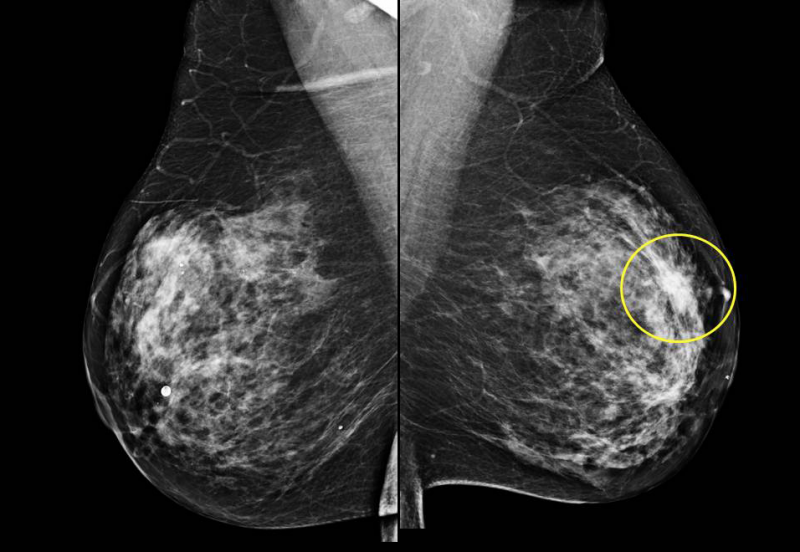

در مقایسه با روش های قدیمی آنالوگ، ماموگرافی دیجیتال مزایایی را برای تشخیص سرطان سینه، به ویژه در زنان کمتر از 50 سال، زنانی که در دوران پیش از یائسگی هستند، و کسانی که بافت سینه متراکمی دارند، ارائه می دهد. تصاویر دیجیتال به جای فیلم به کامپیوتر فرستاده می شوند و به راحتی ذخیره و بازیابی می شوند. تکنسین توانایی بررسی فوری تصاویر را برای تعیین کیفیت دارد، بنابراین بیماران زمان کمتری را در اتاق معاینه می گذرانند. رادیولوژیست می تواند تصاویر را بزرگنمایی کند و کنتر است یا روشنایی را تغییر دهد و اطلاعات بیشتری برای تشخیص ارائه دهد. با دیجیتال، دید بهتری در خط پوست نیز وجود دارد. فناوری تشخیص به کمک رایانه تعبیه شده است که ناهنجاریها را مشخص میکند و در اصل، مجموعه دوم چشمهای رادیولوژیست است.

خود تصاویر ماموگرافی غربالگری اغلب برای تعیین وجود یک بیماری خوش خیم یا بدخیم با قطعیت کافی نیست. در صورت وجود ناهنجاری، رادیولوژیست ممکن است مطالعات تشخیصی بیشتری را توصیه کند.

تفسیر کردن ماموگرافی می تواند دشوار باشد به این دلیل که یک سینه طبیعی برای هر زنی متفاوت به نظر می رسد. همچنین، اگر پودر یا مرهم روی سینهها وجود داشته باشد یا تحت عمل جراحی سینه قرار گرفته باشید، ممکن است ظاهر تصویر به خطر بیفتد. از آنجایی که تجسم برخی سرطانهای سینه دشوار است، ممکن است رادیولوژیست بخواهد تصویر را با نماهای معاینات قبلی مقایسه کند.

افزایش تراکم پستان، مشاهده سرطان در ماموگرافی را دشوار می کند.